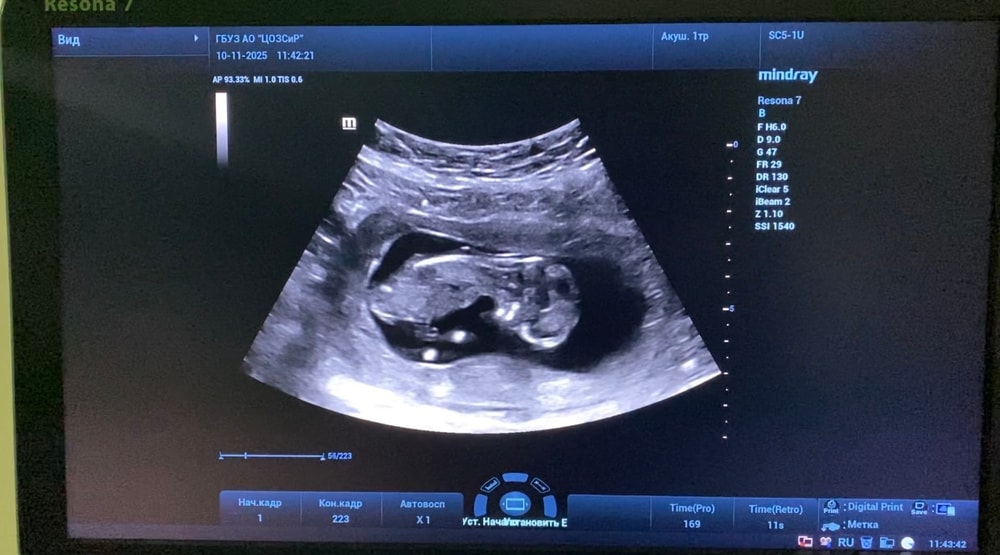

1 скрининг 13+5

Анализы, скринингиНаконец то сходила на 1 скрининг

Малыш развивается хорошо, по крови низкие риски. В целом все хорошо, но есть но.. У пуповины 1 артерия (2 сосуда, вместо 3). Узист успокоила меня, сказала что с малышом все в порядке и это бывает вариантом нормы. Завтра пойду к гинекологу, посмотрим что скажет.

Если тут есть эксперты, делитесь своим мнением какой пол у пупсика :) Попыталась выловить более-менее скриншоты из видео